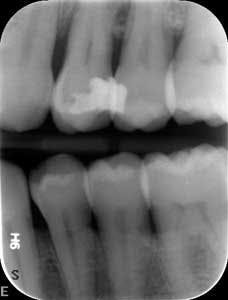

At nine months, the patient’s tissues appeared pink with no inflammation. Radiographs revealed new bone growth, especially around teeth Nos. 3, 15, and 31 (figures 10–12). The patient reported his HbA1c level stable at 8.2.

Radiographs nine months after LANAP treatment (figures 10–12)